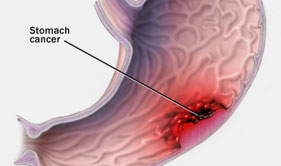

Ulcer disease

GI Cancer